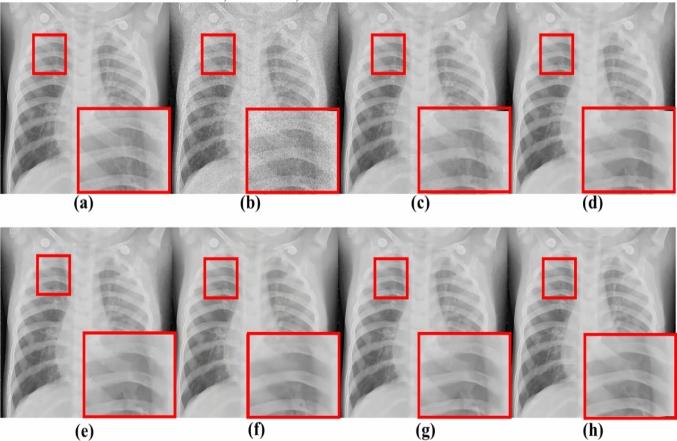

Chest X-ray (CXR) is a medical imaging technology that is common and economical to use in clinical. Recently, coronavirus (COVID-19) has spread worldwide, and the second wave is rebounding strongly now with the coming winter that has a detrimental effect on the global economy and health. To make pre-diagnosis of COVID-19 as soon as possible, and reduce the work pressure of medical staff, making use of deep learning networks to detect positive CXR images of infected patients is a critical step. However, there are complex edge structures and rich texture details in the CXR images susceptible to noise that can interfere with the diagnosis of the machines and the doctors. Therefore, in this paper, we proposed a novel multi-resolution parallel residual CNN (named MPR-CNN) for CXR images denoising and special application for COVID-19 which can improve the image quality. The core of MPR-CNN consists of several essential modules. (a) Multi-resolution parallel convolution streams are utilized for extracting more reliable spatial and semantic information in multi-scale features. (b) Efficient channel and spatial attention can let the network focus more on texture details in CXR images with fewer parameters. (c) The adaptive multi-resolution feature fusion method based on attention is utilized to improve the expression of the network. On the whole, MPR-CNN can simultaneously retain spatial information in the shallow layers with high resolution and semantic information in the deep layers with low resolution. Comprehensive experiments demonstrate that our MPR-CNN can better retain the texture structure details in CXR images. Additionally, extensive experiments show that our MPR-CNN has a positive impact on CXR images classification and detection of COVID-19 cases from denoised CXR images.

胸部X光(CXR)是一种在临床中常用且经济的医学成像技术。近期,冠状病毒(COVID-19)已在全球范围内传播,随着冬季来临,第二波疫情正强劲反弹,这对全球经济和健康产生了不利影响。为了尽快对COVID-19进行预诊断,并减轻医护人员的工作压力,利用深度学习网络检测受感染患者的胸部X光阳性图像是关键一步。然而,胸部X光图像中存在复杂的边缘结构和丰富的纹理细节,容易受到噪声干扰,这可能会影响机器和医生的诊断。因此,在本文中,我们提出了一种新颖的多分辨率并行残差卷积神经网络(名为MPR-CNN)用于胸部X光图像去噪以及针对COVID-19的特殊应用,以提高图像质量。MPR-CNN的核心由几个关键模块组成。(a)多分辨率并行卷积流用于在多尺度特征中提取更可靠的空间和语义信息。(b)高效的通道和空间注意力机制可以让网络在参数较少的情况下更关注胸部X光图像中的纹理细节。(c)基于注意力的自适应多分辨率特征融合方法用于提升网络的表达能力。总体而言,MPR-CNN能够同时在高分辨率的浅层保留空间信息,在低分辨率的深层保留语义信息。综合实验表明,我们提出的MPR-CNN能够更好地保留胸部X光图像中的纹理结构细节。此外,大量实验表明,我们的MPR-CNN对胸部X光图像分类以及从去噪后的胸部X光图像中检测COVID-19病例具有积极影响。